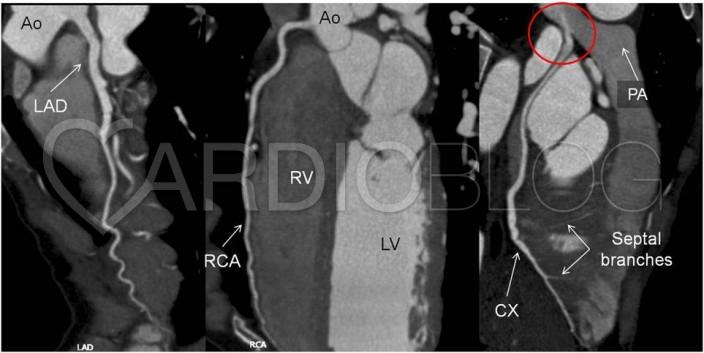

Az elvégzett coronaria CT angiographia tanulsága szerint a coronariák ectaticusak, kanyargós lefutásúak. A kanyarodó multiplanaris rekonstrukciókon jól ábrázolódik a jobb artéria pulmonalisból eredő körbefutó ág (CX). Az artéria pulmonalisban uralkodó nyomás jóval alacsonyabb a coronaria rendszer nyomásánál, így a kontrasztdús vér a CX-ből az arteria pulmonalis irányába áramlik, így a magasabb nyomású coronaria rendszer és az arteria pulmonalis között bal-jobb shunt alakul ki, mely „coronary steal phenomenon” kialakulásához vezet.